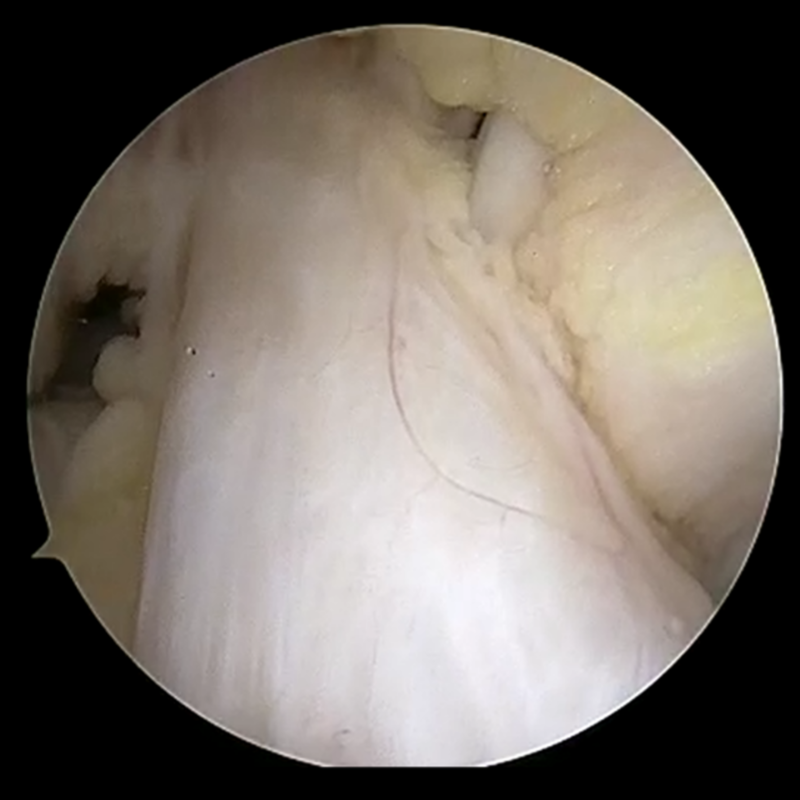

関節鏡では膝関節内に太くしっかりした靭帯としてみることができます。前十字靭帯が損傷してしまうと緊張がなくなり垂れ下がるようになることもあります。